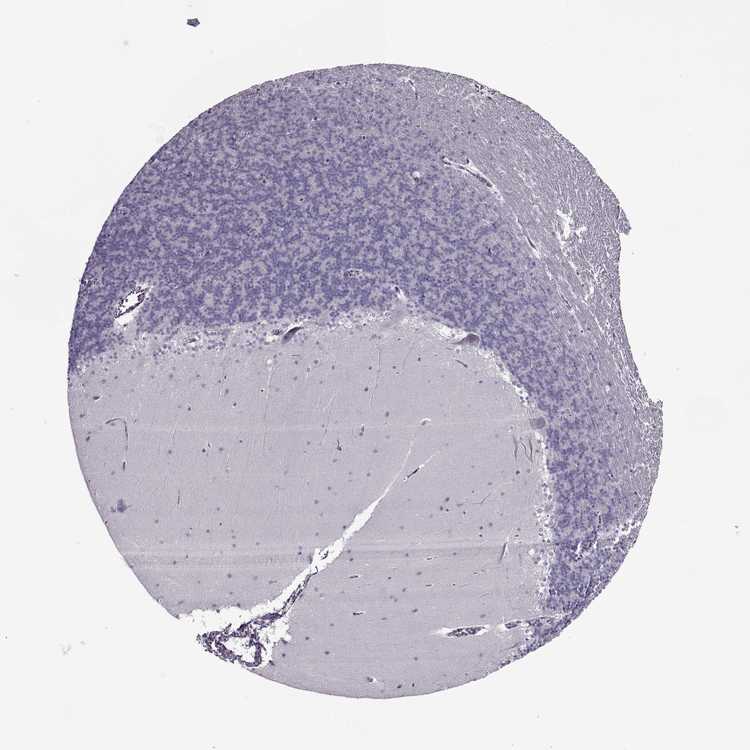

BRAIN CEREBELLUM Show tissue menu

CEREBELLUM - Expression summary

CEREBELLUM - Antibody stainingi

Antibody staining in the annotated cell types in the current human tissue is reported as not detected, low, medium, or high, based on conventional immunohistochemistry profiling in selected tissues. This score is based on the combination of the staining intensity and fraction of stained cells.

Each image is clickable and will lead to virtual microscopy that enables deeper exploration of all samples and also displays staining intensity scores, fraction scores and subcellular localization as well as patient and tissue information for each sample.

Antibody HPA058942

Purkinje cells Not detected

Cells in granular layer Not detected

Cells in molecular layer Not detected